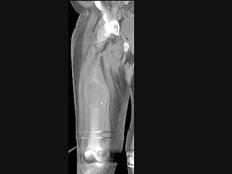

问题 男,18岁,右股骨肿瘤术后,出现大腿中段疼痛,夜间尤甚,结合CT图像,最可能的诊断是?(?)

选项 A.骨纤维肉瘤 B.尤文肉瘤 C.骨肉瘤 D.成骨性骨转移瘤 E.化脓性骨髓炎

答案 C